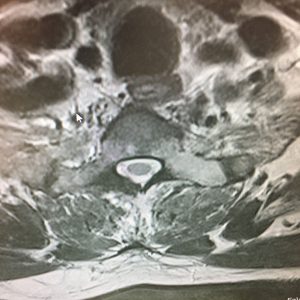

- Παθήσεις Σπονδυλικής Στήλης

- Εκφυλίστικές παθήσεις (Spinal Degenerations)